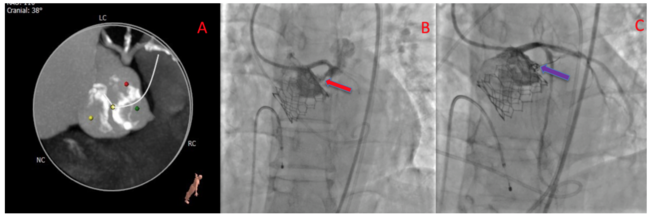

A 78-year-old man with symptomatic bicuspid severe aortic stenosis with LVEF 50% was planned for transcatheter aortic valve replacement (TAVR). His CT scan revealed calcified bicuspid aortic valve (Sievers Type 1), calcified raphe with calcium extending up to annulus (Figure 1A). Annulus area was 508 mm2 while left ventricular outflow tract area was 446 mm2.

Aortogram in co-planar view showed calcified annulus with calcified nodule at raphe. Pre-dilatation was done with 20 mm x 50 mm balloon. A 26 mm Edwards Sapiens 3 valve was deployed under rapid pacing.

Hemodynamics were normal and aortogram showed minimal PVL. Immediately, patient became hemodynamically unstable with electromechanical dissociation. Nonselective left main angiogram showed normal flow to left main but annular rupture in the left coronary sinus (Figure 1B, Video 1). Emergent pericardiocentesis started. Annular rupture site was wired with Fielder FC (Asahi Intecc Medical) and Progreat micro-catheter (Terumo). Nester coil (5/70mm, Cook Medical) delivered into the tract.

The angiogram showed no residual leak (Figure 1C). Patient vitals improved and no effusion was seen with 2D-echo. The patient was discharged on day 3.